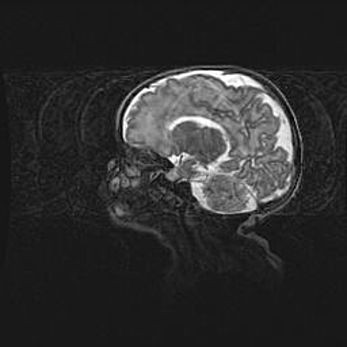

Ниже представлена  галерея МРТ снимков, полученных с применением LMT неонатальных матричных РЧ катушек. Также каждая группа МРТ снимков сопровождается информацией о пациенте (диагноз, возраст, вес, пол, срок гестации) и краткой сопроводительной расшифровкой диагноза.

Аномалия Денди-Уокера. Признаки гипоплазии мозолистого тела.

Возраст: 5 месяцев 3 дня

Вес: 5550 г

Пол: мужской

Окружность головы: 39 см

Срок гестации: 40 недель

Аномалия Денди-Уокера – это порок развития головного мозга, для которого характерна триада симптомов: гипотрофия или аплазия червя мозжечка и/или полушарий мозжечка, расширение четвёртого желудочка с формированием ликворной кисты задней черепной ямки, гипертензионная гидроцефалия различной степени.

Гипоплазия мозолистого тела относится к дефектам внутриутробного этапа развития мозговой ткани, возникающим в процессе закладки структур головного мозга, что происходит на начальных этапах развития эмбриона.